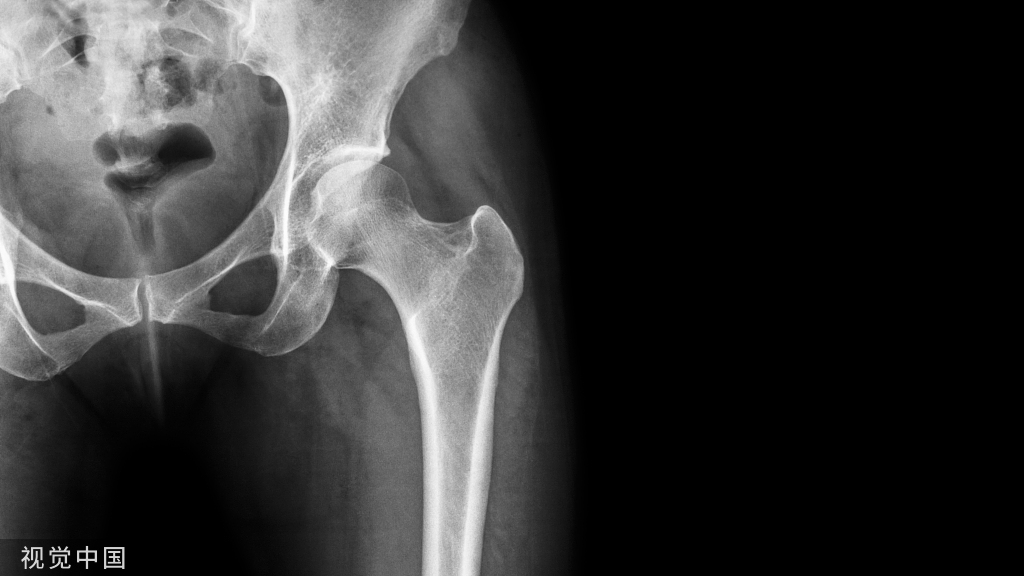

胫骨远端的关节面是不规则形状的矩形,并与距骨的穹顶连接。表面前宽后窄,并且在冠状和矢状平面上都是凹的。胫骨表面与内踝关节表面,约90度到的角度,并连续延伸到胫骨远端约1.5cm。远端腓骨的内侧面也与距骨的外侧面相关联,以完成踝部踝穴。所以,为什么我们固定踝关节的时候要背伸到90度?因为这个时候踝关节最稳定!

胫骨远端的关节面。注意与踝部的关节